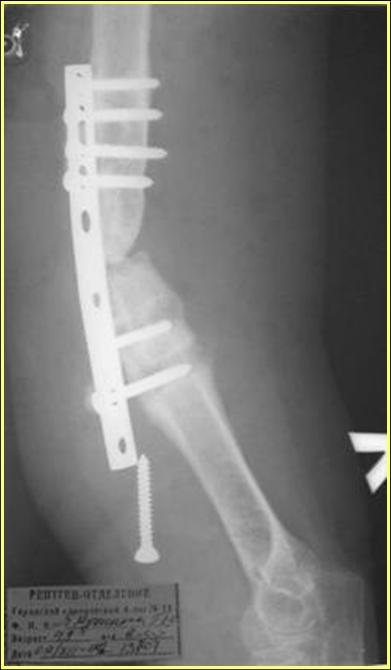

Типичная положительная ситуация для интрамедуллярного остеосинтеза с

использованием опорного металлокаркаса для компенсации дефекта.

Рентгеновская версия реконструкции. хронология:

после операции, 2 мес. после операции, через 1 год